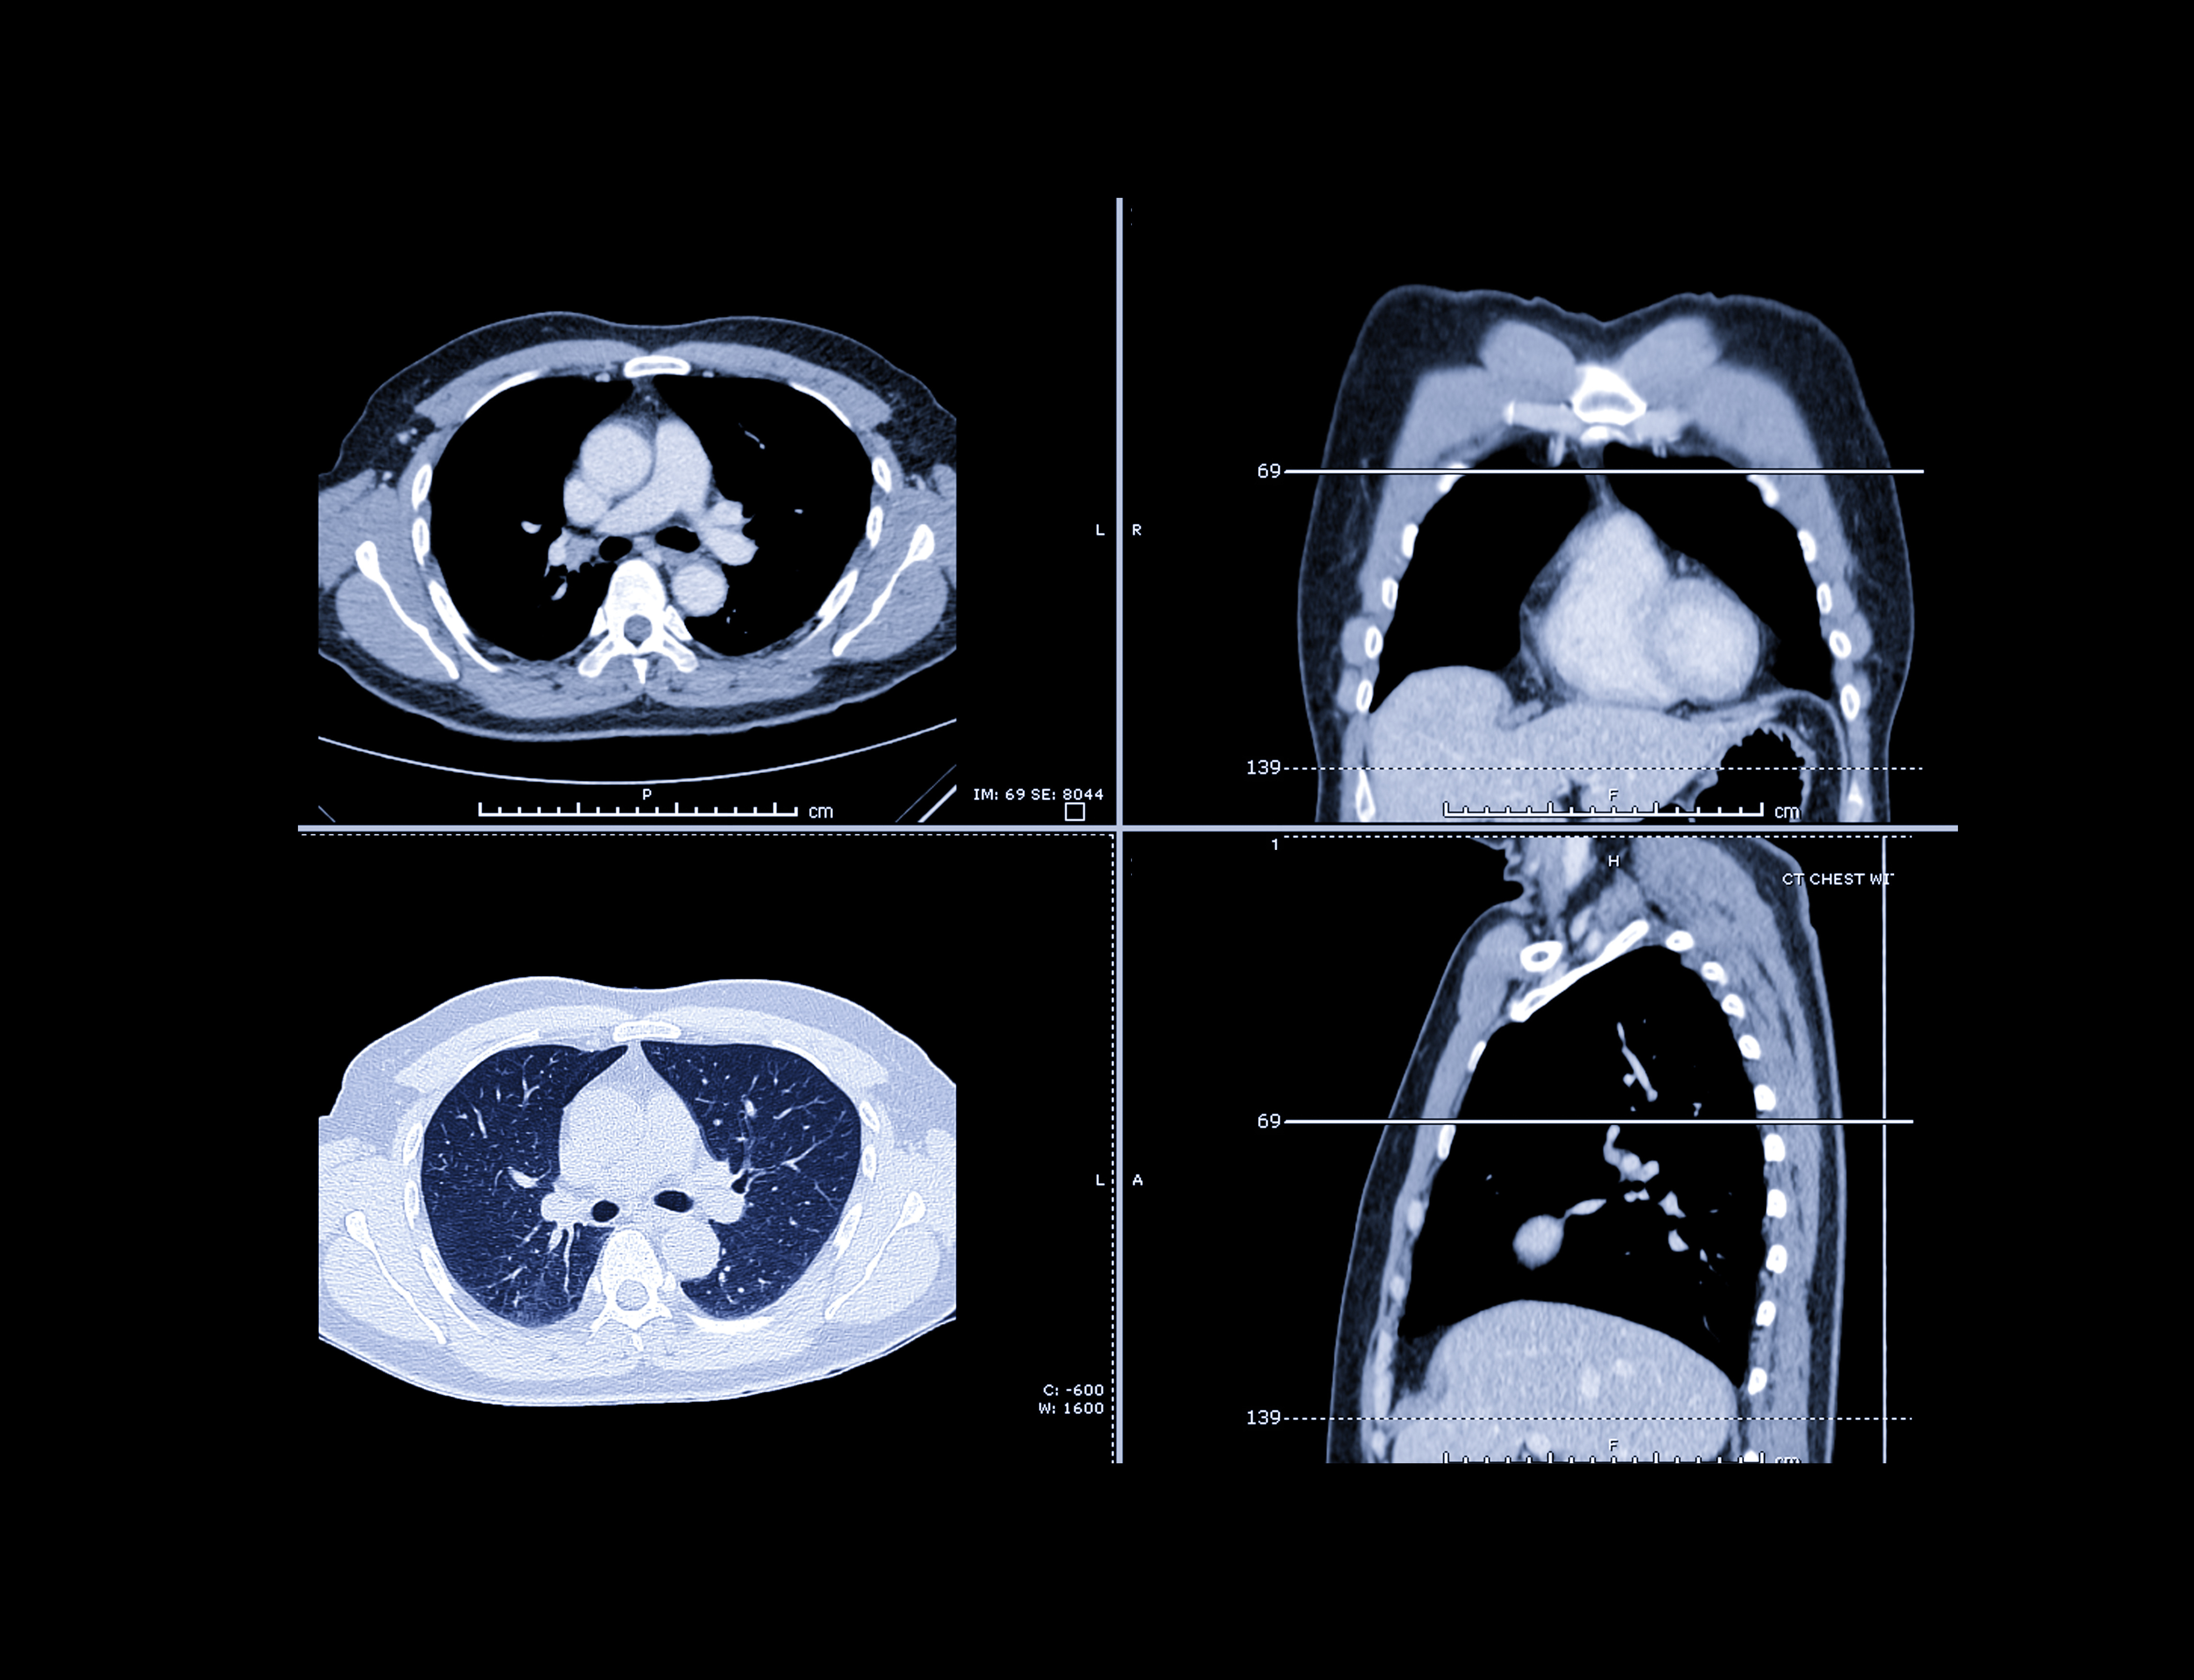

For the study, the investigators first trained a deep-learning model to measure TLC using 50,000 consecutive chest CT scans performed between January 2015 and June 2017 at their institution. They then fine-tuned the algorithm on 3,523 pairs of posteroanterior chest radiographs and plethysmographic TLC measurements from consecutive patients who underwent pulmonary function testing on the same day. To test the model, they used data sets from two tertiary care centers and one from a community hospital that included 217 patients with IPF.

The group found that the difference between TLC on the x-ray images and those estimated by the algorithm were small (0.69 liters vs. 0.73 liters) in the first external test set, and 0.52 liters and 0.53 liters in the second external test set. In the imaging set of 217 patients with IPF, a greater estimated TLC was associated with lower mortality risk (adjusted hazard ratio, 0.97 per percent, p = 0.001), the team found. In the imaging set of 217 patients with IPF, greater estimated TLC percentage was associated with lower mortality risk (adjusted hazard ratio, 0.97 per percent, p = 0.001).